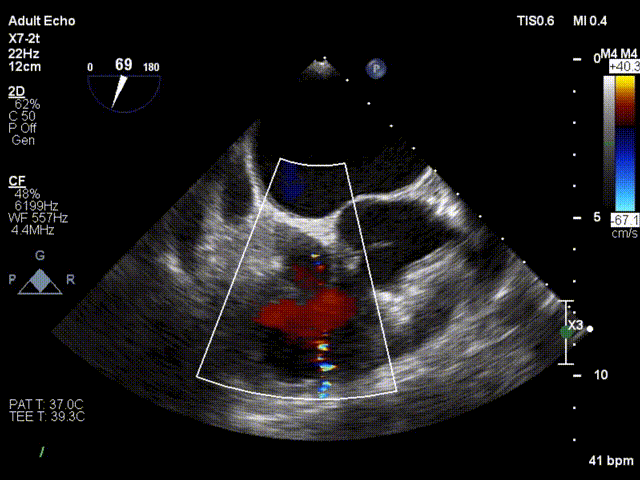

术后超声

仅有微量反流